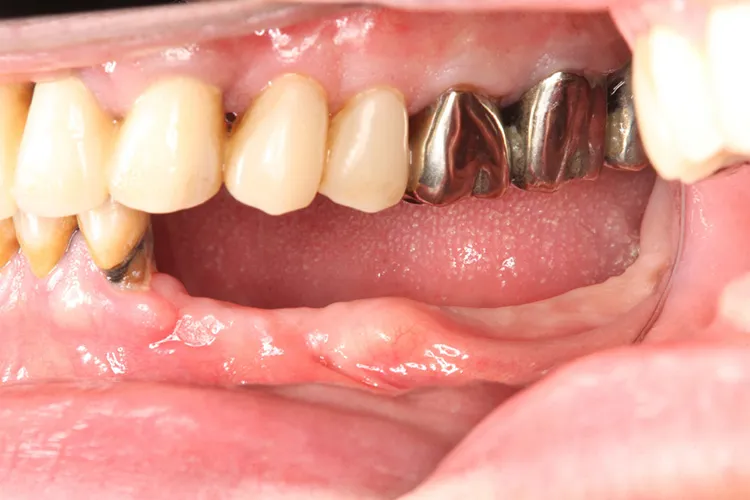

左下5本欠損した部分をインプラント3本埋入して5本ブリッジで治したケースです。なかなかインプラントに踏み切れず、長い間入れ歯を使っておられましたが、噛みごたえがなく好きなものが食べれない上に、度々歯茎が痛んでは調整の繰り返しで快適に過ごすことができず、QOLの向上のためインプラント治療を決断されました。今ではなんでも食べれるとのことで、入れ歯で我慢しないでもっと早くインプラントにすればよかったと言っておられます。